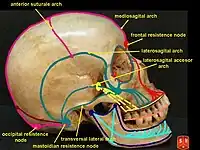

The outer surface of the skull possesses a number of landmarks. The point at which the frontal bone and the two parietal bones meet is known as the bregma. The point at which the two parietal bones and the occipital bone meet is known as the lambda. Not only do these landmarks indicate the fontanelle in newborns, they also act as reference points in medicine and surgery.

It is crossed in front by the coronal suture and behind by the lambdoid suture, while the sagittal suture lies in the medial plane between the parietal bones.